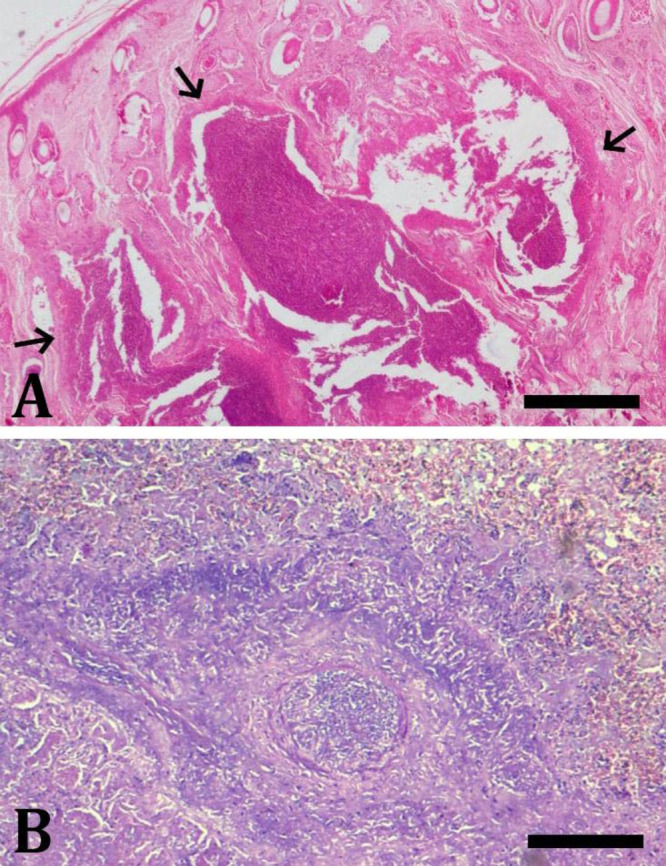

据报道,在印度果阿的一个野生动物保护区,一群四角羚羊(四角羚羊)发生了由坏死梭杆菌感染引起的传染性足腐病暴发。受感染的动物表现出厌食症、跛行和足部损伤的迹象,如蹄子的侵蚀和脱落。2只羚羊的死亡率被记录下来,其中大体病变,如骨骼肌和内脏充血,以及肺、胸膜和隔膜的多灶性合并脓肿。指间皮肤的组织病理学检查显示真皮内有凝固性坏死区、单核炎性细胞浸润、充血、出血和血栓形成。肺显示肺泡水肿、肺泡毛细血管充血、出血和炎症细胞浸润的广泛实变。从心脏血液、肺、肝和肾组织中进行细菌培养,利用扩增necrophorum的lktA基因,聚合酶链反应(PCR)证实了该细菌的分离。此外,PCR还证实了指间皮肤、肺和肝组织中存在坏死镰刀菌DNA。系统发育分析表明,从本研究中分离出的necrophorum分离株与来自澳大利亚、中国、巴基斯坦和伊拉克的分离株以及来自印度山羊的分离株密切相关。受感染的活体动物口服抗生素、抗炎药和维生素补充剂7天后恢复。本研究证实在印度的一群四角羚羊中首次暴发了传染性足腐病和全身感染的坏死羊角菌。

An outbreak of contagious foot rot due to Fusobacterium necrophorum infection was reported in a herd of four-horned antelopes (Tetracerus quadricornis) in a wildlife sanctuary at Goa, India. The infected animals showed signs of anorexia, limping and foot lesions, like erosions and sloughing of hooves. Mortality was recorded in two antelopes in which gross lesions, like generalized congestion of skeletal muscles and internal organs, and multi-focal to coalescing abscesses in lung, pleura, and diaphragm were observed. Histopathological evaluation of interdigital skin showed zones of coagulative necrosis, infiltration of mononuclear inflammatory cells, congestion, hemorrhage, and thrombosis in the dermis. Lung showed extensive areas of consolidation with alveolar edema, hyperemic alveolar capillaries, hemorrhage, and infiltration of inflammatory cells. The bacterial culture from heart blood, lung, liver, and kidney tissues revealed isolation of F. necrophorum being also confirmed by polymerase chain reaction (PCR) using amplification of lktA gene of F. necrophorum. In addition, the PCR also confirmed the presence of F. necrophorum DNA in the interdigital skin, lung, and liver tissues. Phylogenetic analysis showed that the F. necrophorum isolate from the present study grouped closely with isolates from Australia, China, Pakistan, and Iraq, as well as an Indian isolate from goat. The affected live animals were treated with oral antibiotics, anti-inflammatory medicines, and vitamin supplements for seven days, and recovered. This study confirmed the first outbreak of contagious foot rot and systemic infection with F. necrophorum in a herd of four-horned antelopes in India.